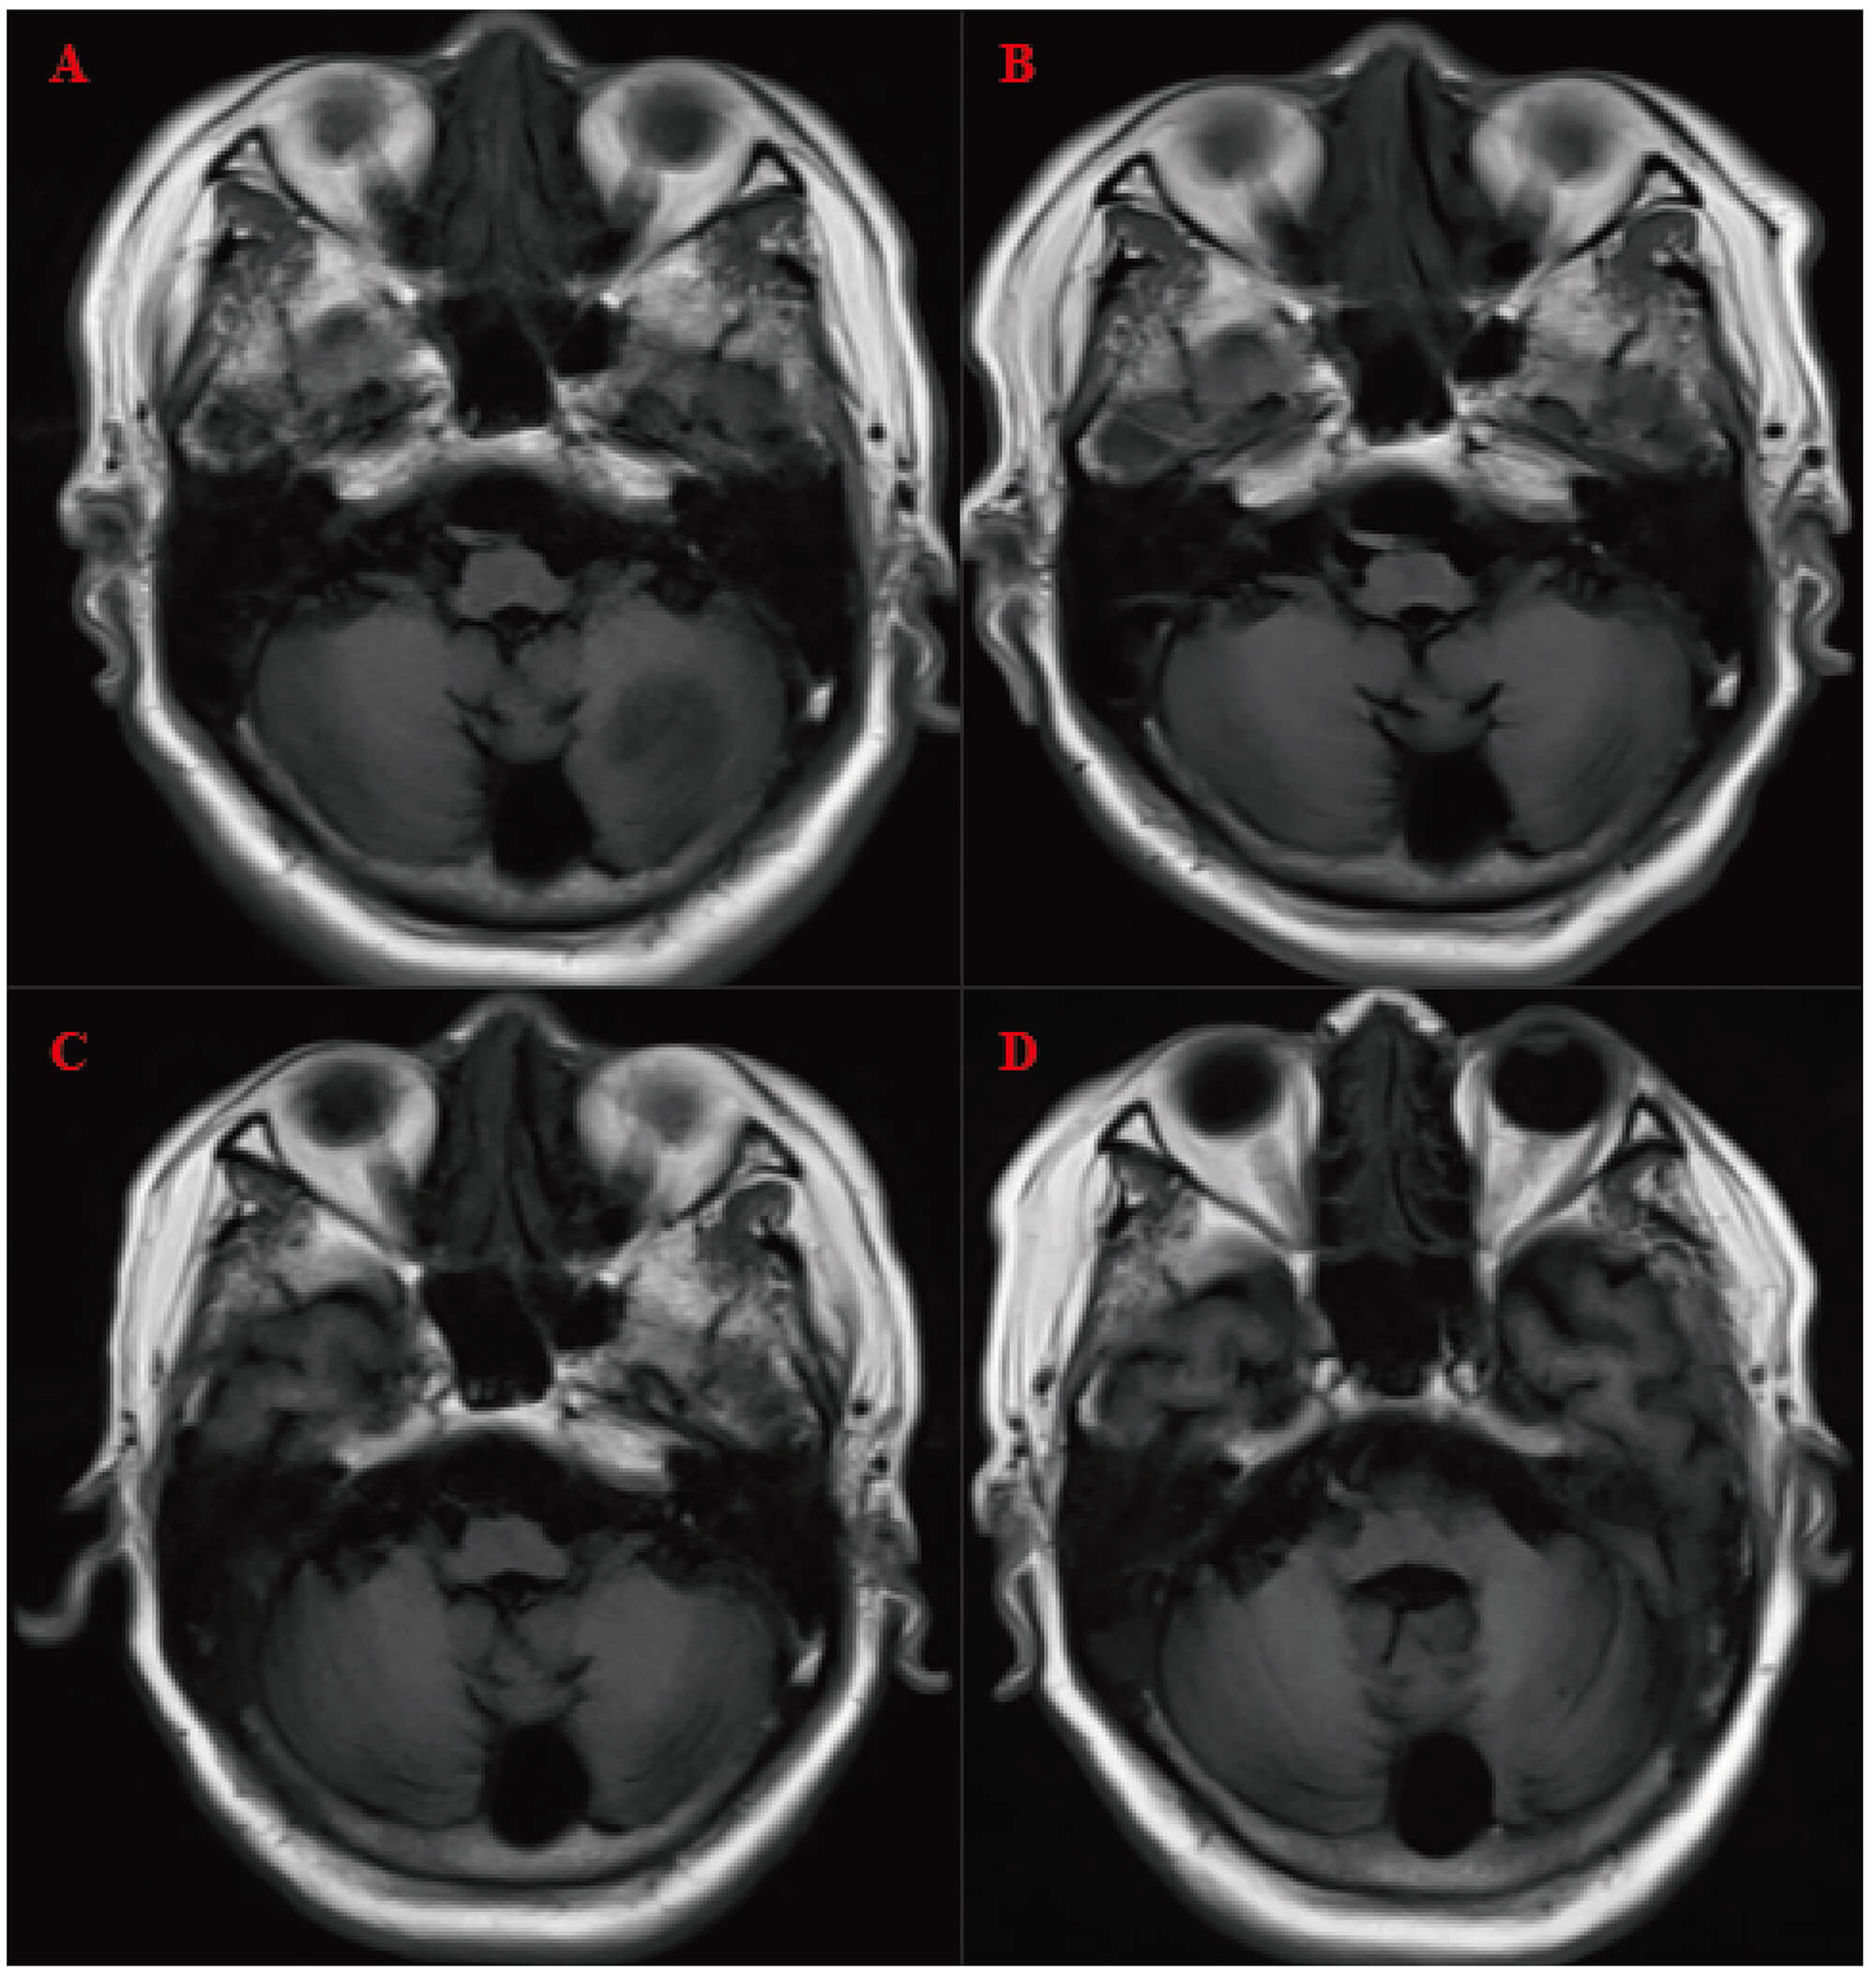

A follow-up brain MRI in March 2025 showed a metastatic lesion in the left cerebellar hemisphere, for which whole-brain radiotherapy was subsequently administered. Contrast-enhanced brain MRI (Fig. 6) later demonstrated gradual resolution of the left cerebellar metastasis (no visible lesion was detected in August). Multiple lacunar foci were observed in the basal ganglia, corpus callosum, brainstem, and left thalamus, along with white matter rarefaction, confirming the efficacy of whole-brain radiotherapy and excluding alternative neurological causes.

Fig. 6.

Contrast-enhanced brain magnetic resonance imaging (MRI). (A–D) were obtained on 18 March, 25 April, 12 May, and 23 August 2025, respectively, demonstrating gradual absorption of the left cerebellar metastatic lesion following whole-brain radiotherapy.